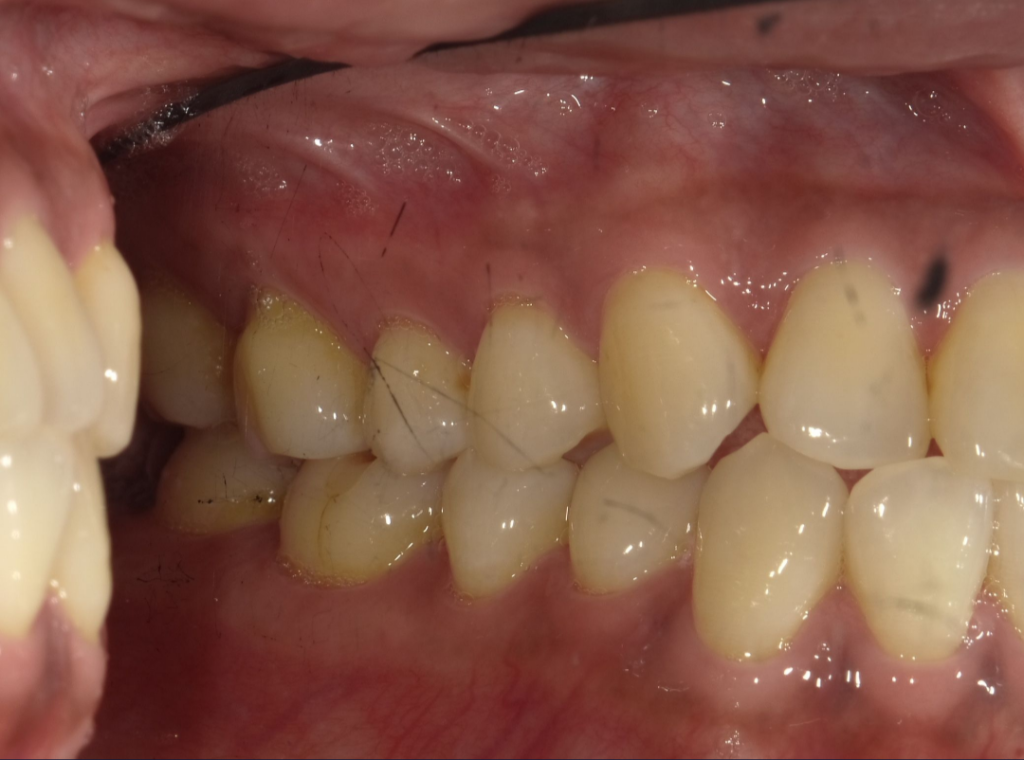

結果がこちら。(歯の画像は初日の治療前なので汚くて申し訳ございません)

前の歯は今のところ問題ないけど、後ろの歯周ポケットが最長5mmと結構下がってて歯周病になりつつあるから予防治療を勧めると。

でもさ、5mm下がってるのは分かるけど、ちょっとこの資料、印象操作が過ぎん!?!?ww実際、奥歯こんな根っこ見えてないけどな?!wと、心の中で思うはの子だったが